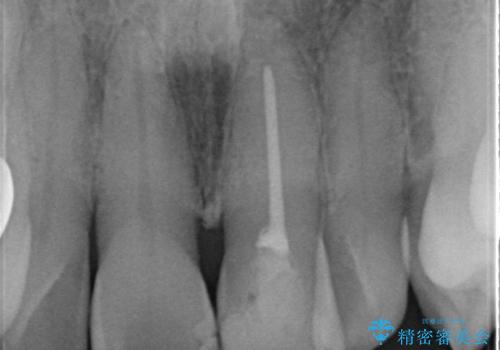

神経の治療をした歯は時間の経過と共に色調の変化が見られます。

このような際、ジルコニアクラウンを装着することで審美性の改善を達成することができます。